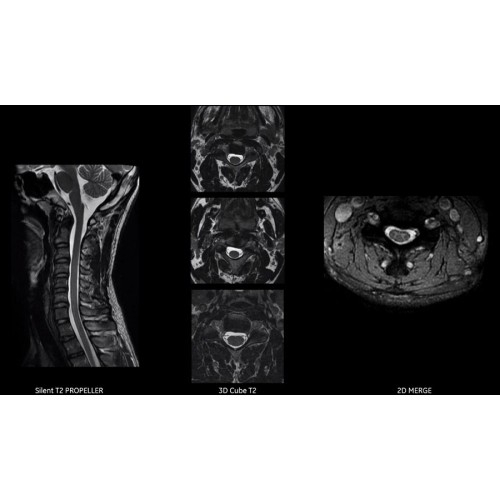

Благодаря революционному программному пакету Silent Suite уровень шума снижается до 77 дБ, что всего на 3 дБ выше уровня окружающей среды. Программный пакет Silent Suite теперь включает полный пакет приложений для исследования ЦНС (T1, T2 FLAIR, DWI10, МРА). Кроме того, мы расширили возможности визуализации Silent за пределы ЦНС для исследований скелетно-мышечной системы и позвоночника. Silent Suite – платформа, содержащая в себе все импульсные последовательности для бесшумного сканирования.

Технологии SIGNA Pioneer позволяют проводить полное исследование брюшной полости при свободном дыхании, минимизируя артефакты движения пациента, в том числе с МР-динамическим контрастированием.